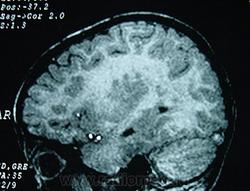

Гетеротопии. Перивентрикулярная гетеротопия. Субэпендимальная нодулярная (узелковая) гетеротопия.

Наиболее частым вариантом миграционных нарушений является гетеротопия - скопление нейронов, остановившихся в различных аномальных местах на пути следования к коре головного мозга. Такая остановка происходит не позже 5-го месяца внутриутробного развития. Изолированный участок узловатой массы называется «гетеротопион». В настоящее время описаны следующие варианты гетеротопии:

Перивентрикулярная субэпендимальная гетеротопия